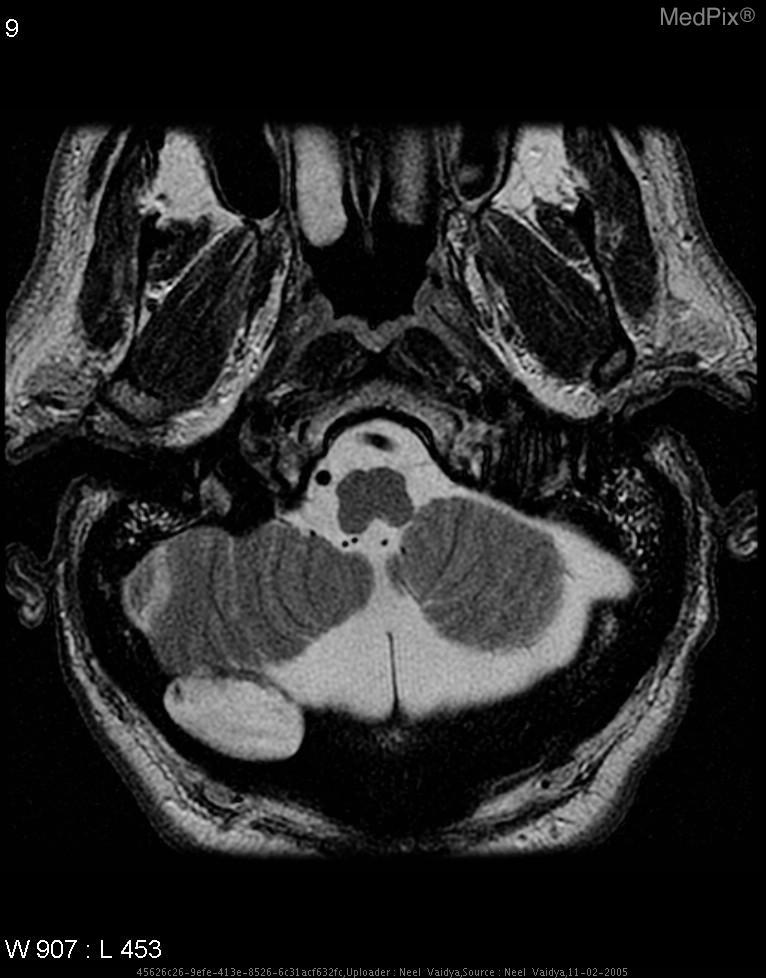

Refer to caption

Figure 3: Dataset composition and evaluation framework. The distribution of question types and datasets is shown together with sensitivity analyses and correlations by type. Representative prompt cards illustrate the baseline task and each pressure type. The right hand plots summarize overall sensitivity by type, providing context for the balanced challenge set construction and subsequent evaluation.

2.4 Mechanism and control analyses

We probe whether sycophancy reflects a pervasive mechanism rather than incidental prompt artifacts. First, evaluation is stratified by question type and dataset composition (Fig. 3a). Sensitivity analysis shows consistent ordering across types: short form responses such as yes/no and where style queries are most susceptible, whereas organ system questions are least affected (Fig. 3c). Second, across models, higher baseline accuracy does not eliminate sensitivity; the relationship between initial accuracy and sycophancy sensitivity is weak to moderate and persists after accounting for sample size (Fig. 3d). Third, the baseline accuracy and overall sycophancy are only weakly coupled (Fig. 2b), reinforcing that interaction robustness is a distinct axis from task competence.

Figure 3 elaborates these controls and provides the context for type specific effects. The annular summary (left) confirms that the challenge set draws from PathVQA[8], SLAKE[15] and VQA-RAD[12] with balanced coverage across organ systems and question forms (yes/no, where, what/how, abnormality, object). This balance ensures that the observed vulnerabilities are not artifacts of dataset skew. The type level sensitivity plots (right) show that short form prompts with narrow answer spaces (for example, yes/no and where) are disproportionately affected by social pressure, whereas items that require richer evidence extraction or organ level reasoning are comparatively robust. Representative prompt cards in the center panel illustrate how each of the seven pressure types perturbs the linguistic context while leaving the visual evidence unchanged, highlighting the risk of decoupling external social cues from image grounded reasoning.

Across datasets the ordering of sensitivities remains stable, indicating that these effects generalize rather than reflect idiosyncratic properties of a single source. Together with the positive correlations among types (Fig. 2, correlation panel), these results suggest a shared compliance mechanism: when social signals are salient and the task surface admits concise answers, models tend to reweight away from visual evidence. This observation directly motivates our mitigation strategy to center inference on image evidence regardless of conversational framing.